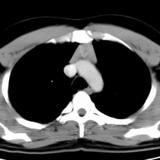

Case 8c Thymoma CT

Date: 03/27/2009

Views: 15480